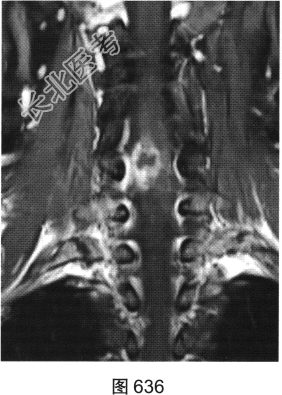

- [材料题] 患者女性,49岁,颈部胀痛伴双手麻木3天。MRI检查见图632~图637。

- 多项选择题1.患者MRI图片有哪些阳性征象( )

A、同水平硬膜囊及脊髓明显受压

B、病变与硬膜夹角为钝角

C、病变呈环形强化,中心未见明显强化

D、病变在髓外硬膜下

E、病变跨越右侧椎间孔,呈哑铃状改变

F、C

水平硬膜外梭形软组织信号

- 多项选择题2.根据MRI表现,患者可能的诊断是( )

A、脊柱淋巴瘤

B、椎间盘脱出、髓核游离

C、神经纤维瘤

D、后纵韧带骨化

E、神经鞘瘤

F、硬膜外血肿